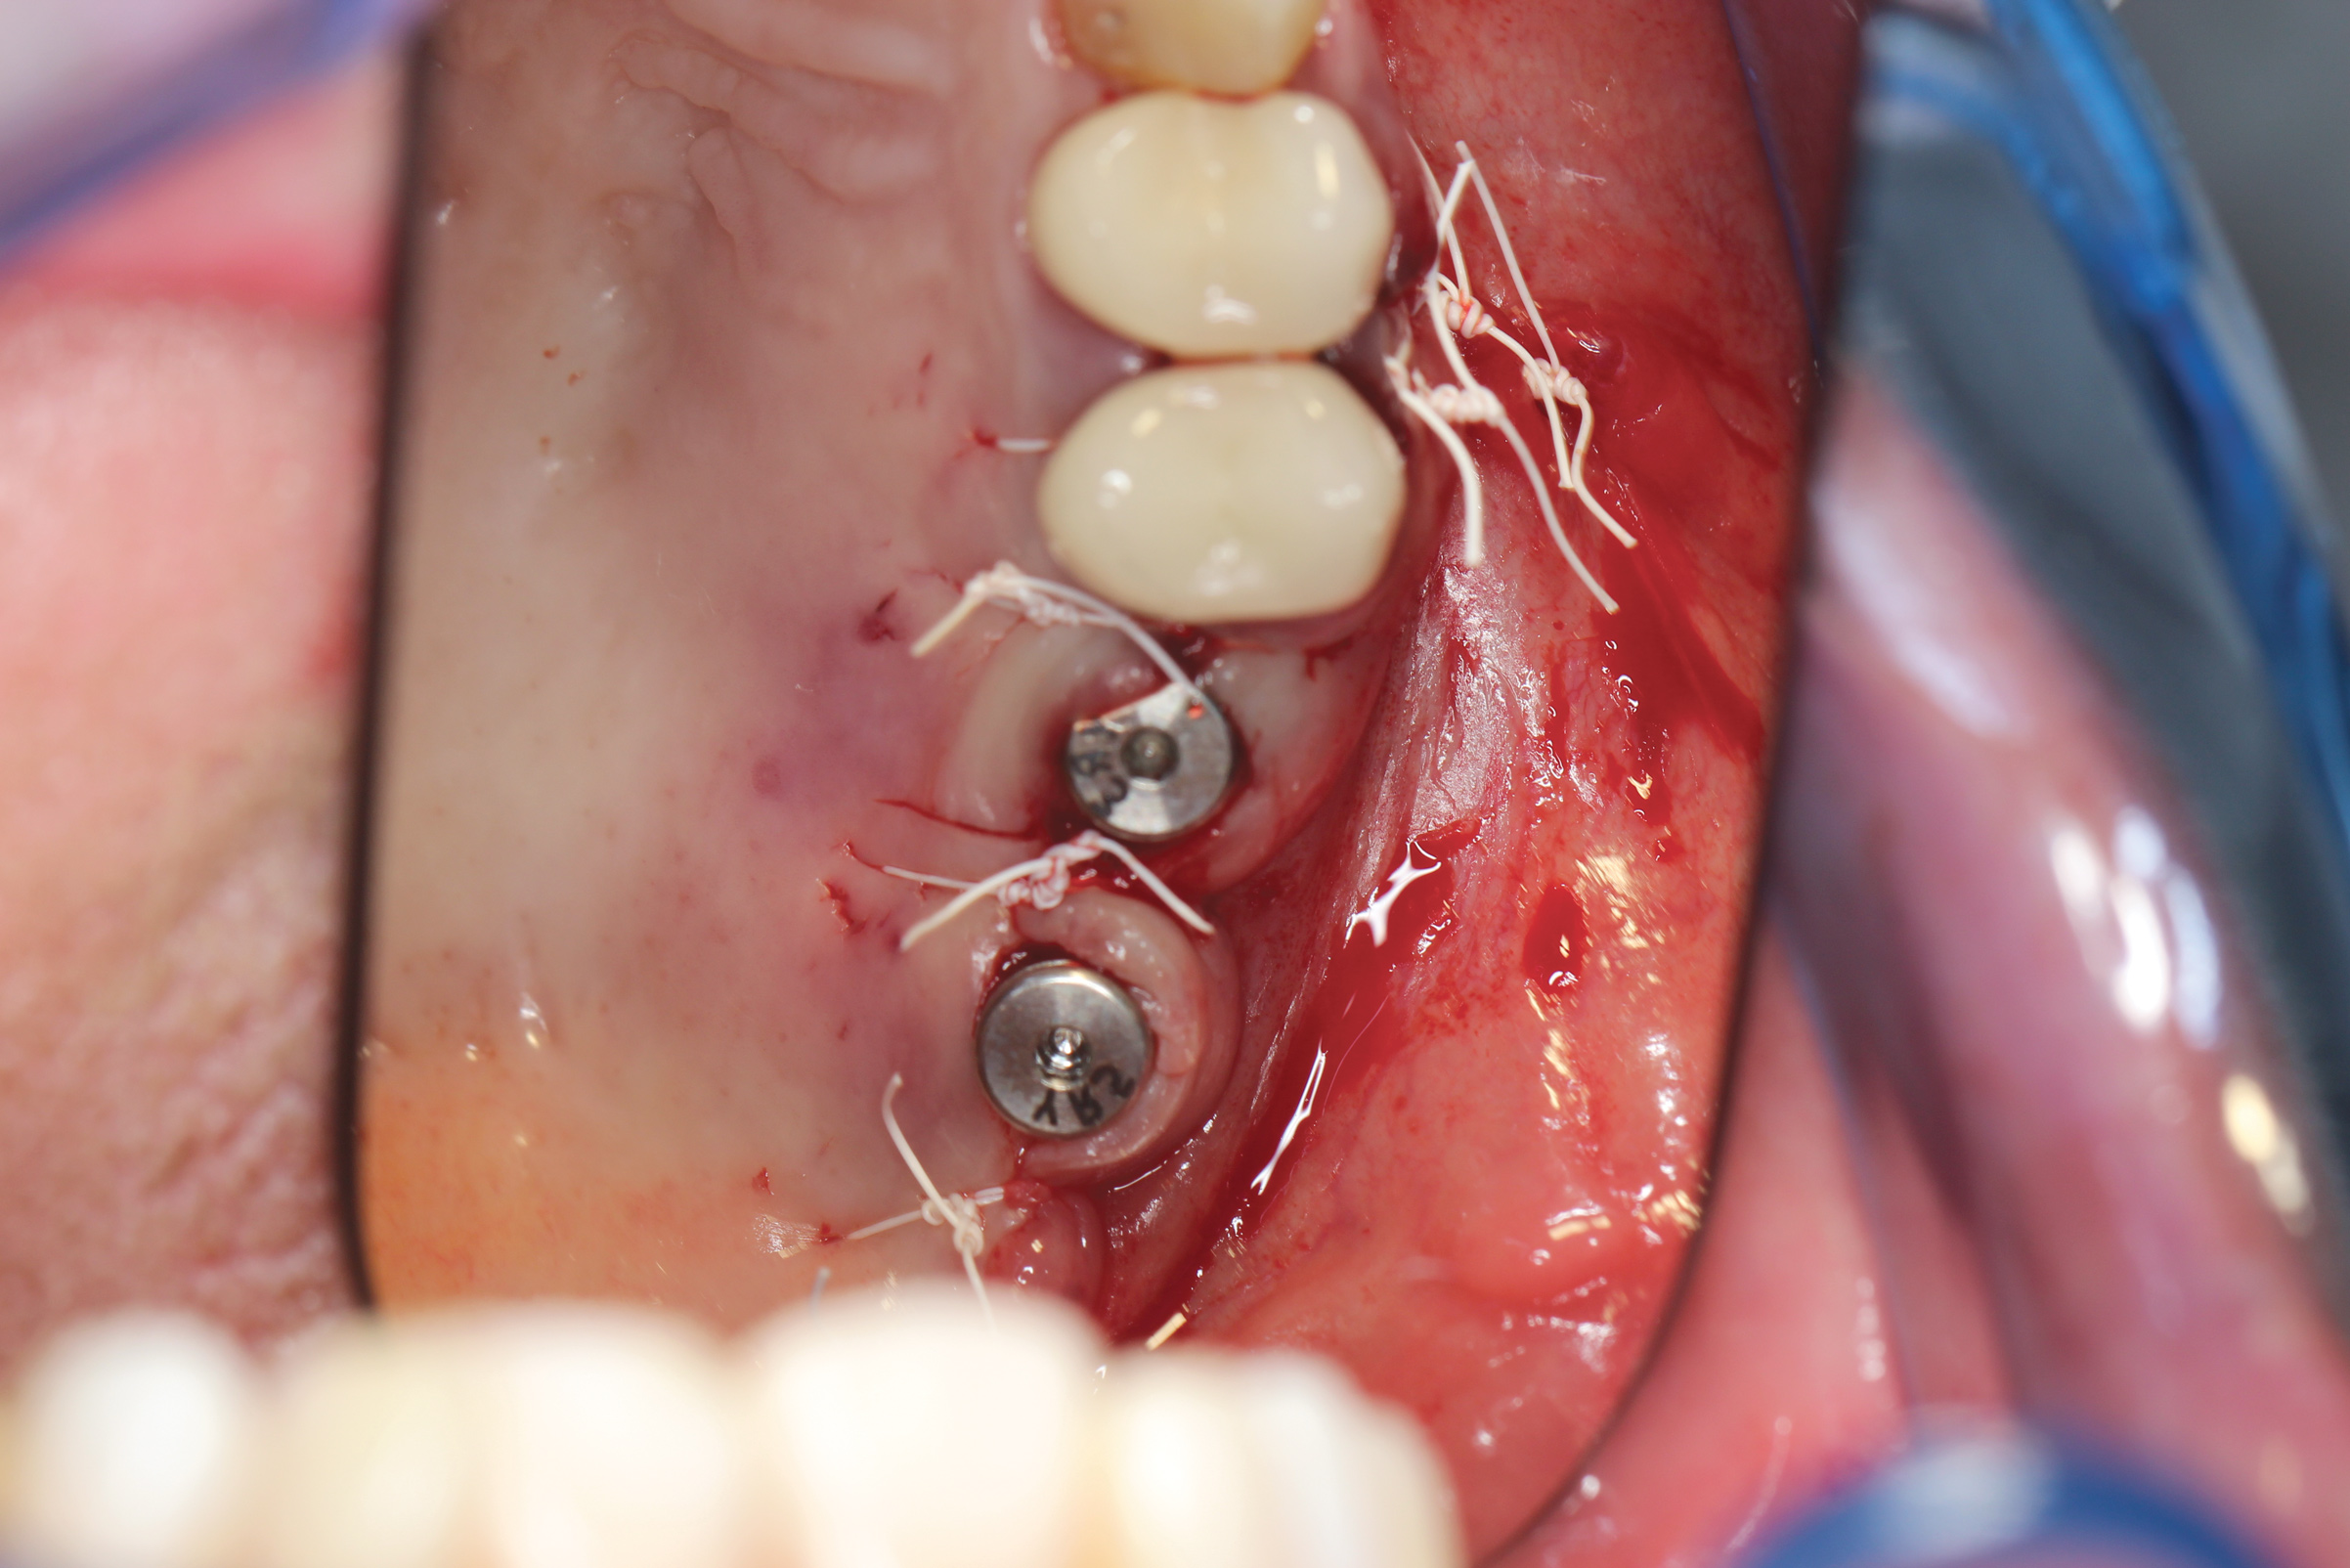

Fig 10. Clinical image demonstrating loss of maxillary left first bicuspid along with a resorbed posterior ridge.

Figure 10

Fig 11. OD burs were used to create osteotomy.

Figure 11

Fig 12. Bone grafting putty was placed inside the osteotomy.

Figure 12

Fig 13. OD bur was used in counterclockwise mode to propel the bone graft putty apically and circumferentially beneath the sinus membrane.

Figure 13

Fig 14. After implant placement, soft-tissue closure was accomplished with 3.0 PTFE suture.

Figure 14